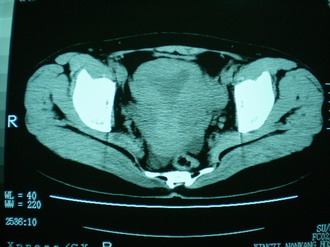

子宫增大,内可见类三角形低密度区,子宫后方可见类圆形团块状影,内部密度不均匀,可见靶样结构,结合病史考虑1子宫后方宫外孕(宫内假孕囊形成)2子宫肌瘤合并妊娠

子宫明显前倾,增大,宫颈增大呈分叶状。子宫直肠窝见不规则形水样低密度。(膀胱胀尿不理想)

考虑:1、宫颈部占位;

2、子宫直肠窝少量积液(盆腔炎所致)。

支持子宫后浆膜下型肌瘤,

宫颈部肌瘤宫腔内积血,

1、前曲子宫,2、宫颈部占位?3、盆腔及右输卵管积液?宫内积血?4、左侧卵巢囊肿。